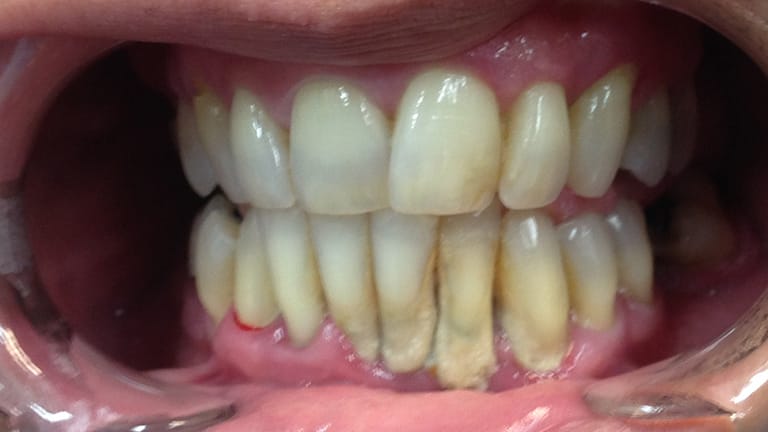

Below is a few examples of what DENTAL IMPLANTS can do for you and your smile!